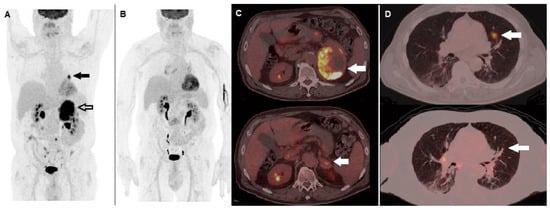

- Iravani, A.; Osman, M.M.; Weppler, A.M.; Wallace, R.; Galligan, A.; Lasocki, A.; Hunter, M.O.; Akhurst, T.; Hofman, M.S.; Lau, P.K.H.; et al. FDG PET/CT for Tumoral and Systemic Immune Response Monitoring of Advanced Melanoma during First-Line Combination Ipilimumab and Nivolumab Treatment. Eur. J. Nucl. Med. Mol. Imaging 2020, 47, 2776–2786. [Google Scholar] [CrossRef]

- Ramos-Casals, M.; Brahmer, J.R.; Callahan, M.K.; Flores-Chávez, A.; Keegan, N.; Khamashta, M.A.; Lambotte, O.; Mariette, X.; Prat, A.; Suárez-Almazor, M.E. Immune-Related Adverse Events of Checkpoint Inhibitors. Nat. Rev. Dis. Primers 2020, 6, 38. [Google Scholar] [CrossRef]

- Fujii, T.; Colen, R.R.; Bilen, M.A.; Hess, K.R.; Hajjar, J.; Suarez-Almazor, M.E.; Alshawa, A.; Hong, D.S.; Tsimberidou, A.; Janku, F.; et al. Incidence of Immune-Related Adverse Events and Its Association with Treatment Outcomes: The MD Anderson Cancer Center Experience. Investig. New Drugs 2018, 36, 638–646. [Google Scholar] [CrossRef]